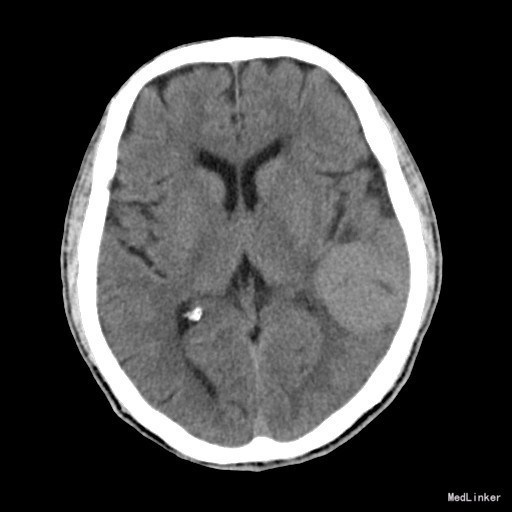

主诉:头晕、言语不清2月余 病史:老年男性,亚急性起病。患者2月余前无明显诱因出现头晕、言语不清,无头痛,遂至当地医院就诊,行头颅MR结果示:左颞部脑膜瘤。现患者为求进一步诊治来我院我科住院治疗。

查体:神志清楚,查体合作,理解力正常,言语不清、欠协调,视力视野未见异常,病理反射未引出,无脑膜刺激征。 辅查:左侧颞叶肿块,考虑肿瘤性病变,脑膜瘤可能性大。

诊断:脑膜瘤 治疗:行“左侧颞顶占位病变切除术”,术后恢复良好。

随访:术后病理追踪:(脑膜瘤)镜下见肿瘤由梭形细胞构成,部分细胞呈漩涡样排列,细胞有异型性,核分裂象罕见,结合免疫组化,可符合脑膜瘤(WHOⅠ级)。 讨论:脑膜瘤是颅内常见肿瘤之一,来源于硬膜内的蛛网膜绒毛细胞,绝大多数为良性,起病缓慢,病程长。影像上一般诊断不难,CT上表现为:肿瘤位于脑外,以宽基底与颅底或硬脑膜相连,平扫呈等或高密度,呈圆形或卵圆形,增强扫描均匀明显强化。